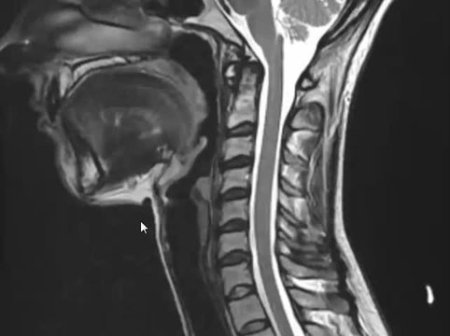

Se realiza un breve interrogatorio. Un examen físico para evaluar la región del dolor, la movilidad, la fuerza, la sensibilidad y se realizan radiografías cervicales y de ser necesario una resonancia magnética nuclear (RMN).

- estructura ósea (fractura, luxaciones, artrosis),

- estructura neurológica (médula espinal, nervios cervicales),

- estructura discal (protusiones, hernias discales),

- postura cervical (rectificación, inversión).